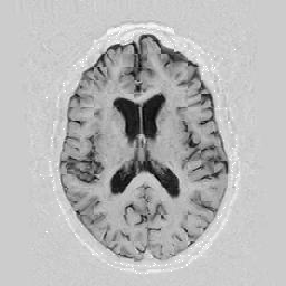

Lastly, Figure [*] shows 10 iterations at level 2, 6 iterations at level 1, and 6 at level 0.

Figure: Multi-scale NRR. From left to right, top then bottom: before NRR; after 10 iterations of NRR at level 2; after another 6 iterations of NRR at level 1; after 6 more iterations at level 0.